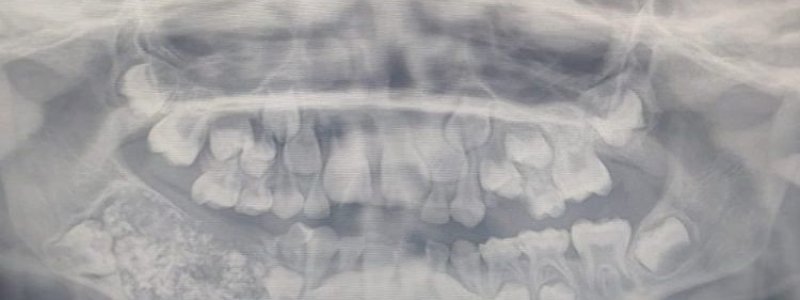

Kemunculan gigi-gigi yang tumbuh tidak pada tempatnya memang gejala yang sering ditemukan di beberapa orang dengan menderita sakit gigi.